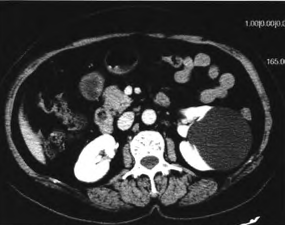

入院查体:生命体征平稳,心肺腹查未见明显异常。 双肾CT平扫+增强::双肾各见一枚囊状低密度灶,较大一枚位于左侧,大小为7.5cm×8.0cm,边界尚清,内见钙化灶,增强扫描未见强化双肾无水,未见阳性结石影。